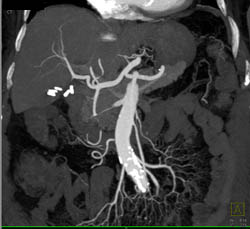

Cholangiocarcinoma of the Distal Common Bile Duct (CBD) Which Is Enhancing- See Full Sequence